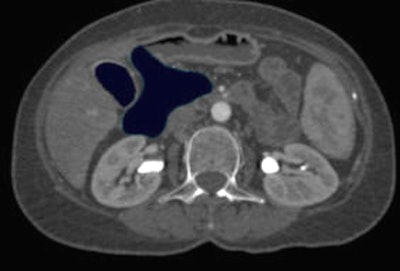

![]() |

| Above, the removal procedure is then repeated for the pancreas and duodenum using MPRs (below) to avoid accidentally removing critical structures. |